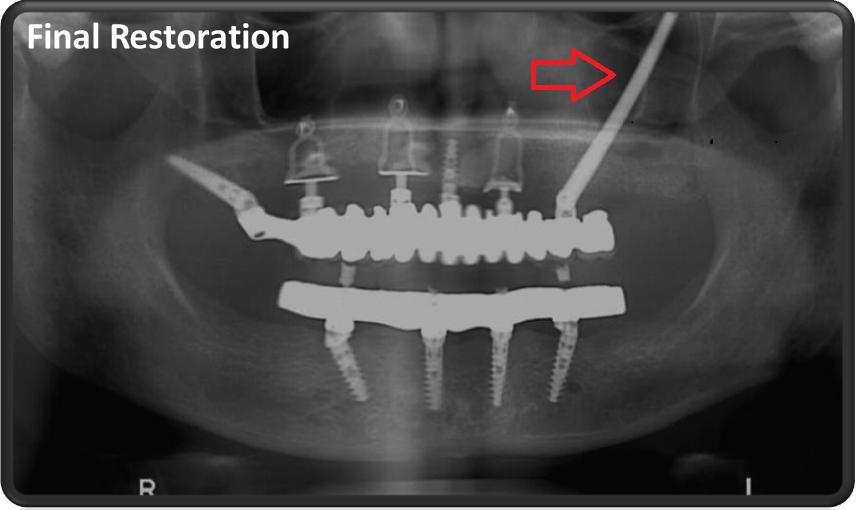

השתלת שתלים זיגומטיים במצב של חוסר עצם